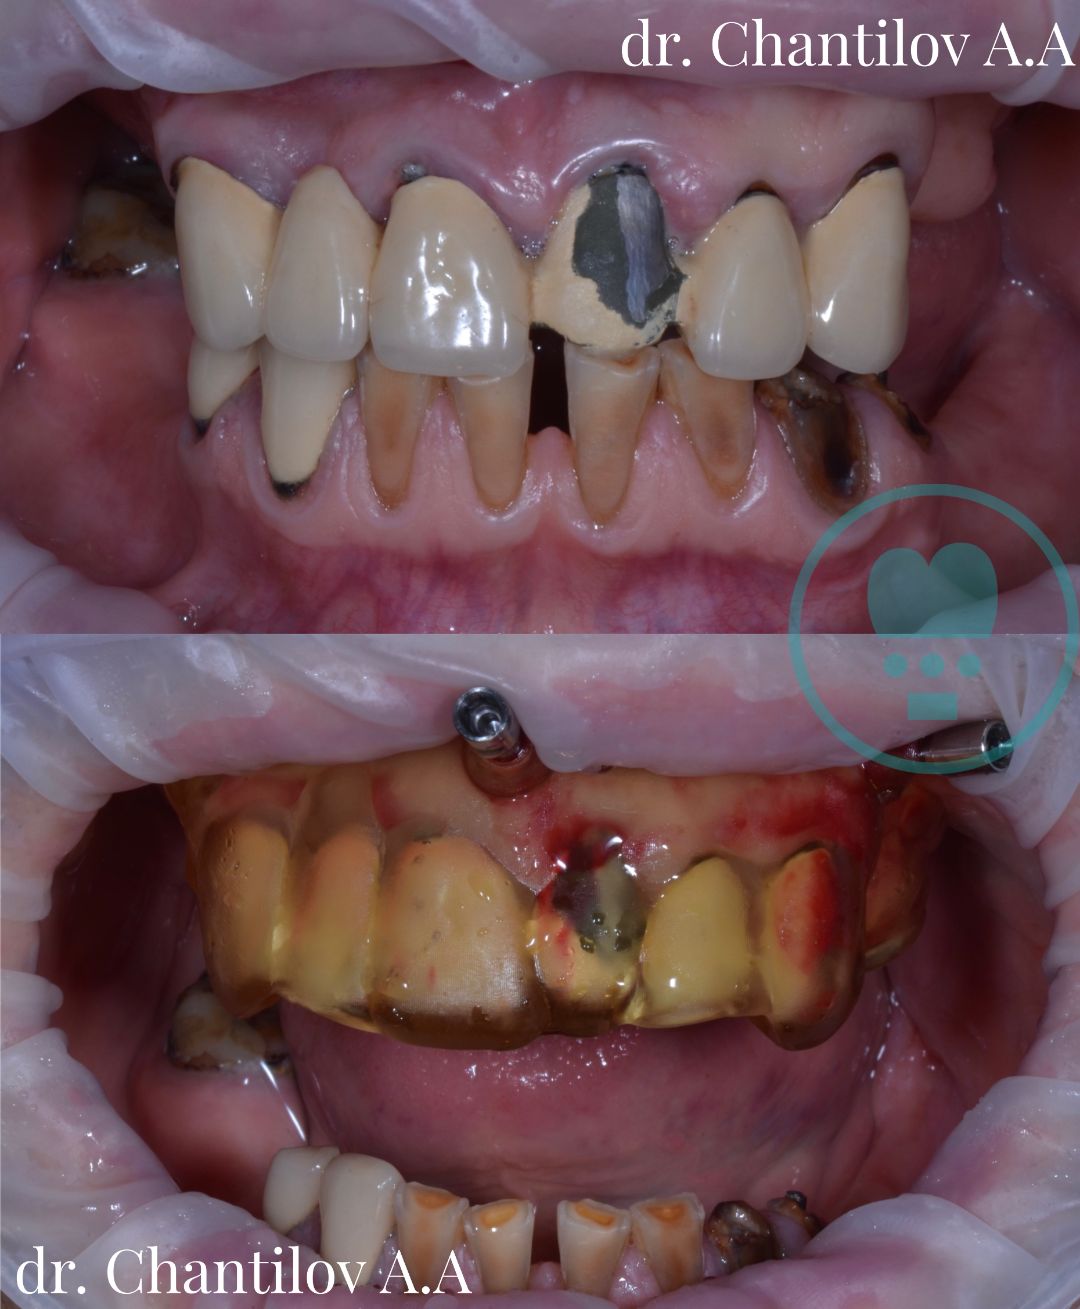

Имплантация зубов челюсти - фото до и после

Изготовление индивидуального шаблона